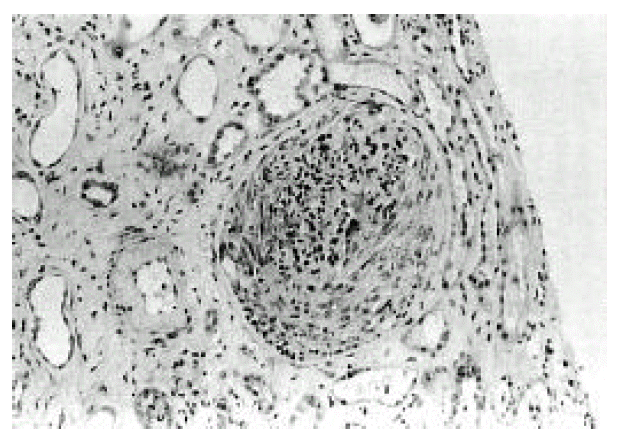

Figure 3.

IF shows a diffuse granular staining with anti-IgG and anti-C3 along the capillary wall

A 66-year-old man was admitted to Keimyung University Hospital because of decreased urine output and right upper quadrant pain. Seven years earlier, he had a Whipple’s operation for obstructive jaundice due to Ampulla of Vater cancer. At that time, the pathology report showed a moderately differentiated adenocarcinoma and biopsies of the regional lymph nodes showed no evidence of metastasis. At that time, renal function was normal and the urine contained no proteins or red cells. Two weeks before admission, the patient developed right upper quadrant dull pain, nausea, anorexia, myalgia, chills and fever. Four days prior to admission, he noticed gross hematuria, marked decrease in urine output and edema in lower extremities. On admission, his body temperature was 36.4°C and blood pressure was 110/60 mmHg. Daily urine output ranged 800–1200 mL. Face was puffy. He did not have icterus. His conjunctivae was slight anemic and revealed several petechial hemorrhages. Auscultation of the lung revealed bilateral basilar rales. No murmurs or frictions were heard. The liver was enlarged and tender. There was no splenomegaly or rash. There was marked costovertebral angle enderness. here was mild pretibial edema. Laboratory data on admission showed WBC 34,600/mm3, hemoglobin 8.3 g/dL, platelet count 95,000/mm3, BUN 16.4 mmol/L, serum creatinine 985,6 μmol/L, cholesterol 118 mg/dL, total bilirubin 3.4 mg/L, alkaline phosphatase 270 IU/L, SGPT 18 IU/L, and serum albumin 2.0 g/dL and creatinine clearance 2.5 ml/min. Urinalysis showed specific gravity 1.020, protein 2+, and urinary sediment containg two granular casts, many red blood cells and 10 white blood cells/HPF. The 24-hour urinary protein excretion was 2.4 gm and FENa was 1.7%. C3 level was 0.67 g/L (normal range: 0.8–1.2 g/L) and C4 level was 0.46 g/L (normal range: 0.2–2.5 g/L). Cryoglobulin was absent. The tests for hepatitis B and C, antinuclear antibody and rheumatoid factor were negative. Chest radiographs demonstrated bilateral perihilar pulmonary congestions. On admission, he was afebrile. He had obvious pulmonary edema as well as peripheral edema. Immediate hemodialysis resulted in a weight loss of 2 kg and respiratory improvement. Ultrasonographic examination of liver showed ill marginated cystic mass in left lobe. Computed tomography (CT) of the abdomen demonstrated 7×5cm sized multiple septated lower density lesions in medial segment of left lobe of the liver (Figure 1). Numerous blood cultures were negative. Initially the patient was treated with diuretics, albumin infusions and antibiotics (sulbactam/cefoperazone and aztreonam). On the 15th day, percutaneous needle biopsy of the kidney was performed. Light microscopy showed 17 glomeruli with two global sclerosis. The glomeruli showed endo-and extracapillary proliferation (Figure 2), with cellular crescents involving 25% of the glomeruli. The interstitium showed diffuse edema and no tubular necrosis. Immunofluorescent examination showed a diffuse granular staining with anti-IgG and anti-C3 along the capillary wall, and no staining with anti-IgM or anti-IgA (Figure 3). Needle aspiration of the liver was performed on the 19th hospital day, with the drainage of greenish pus material. Culture of the liver aspirates later grew Pseudomonas aeruginosa. Ticarcillin was given. The patient improved substantially. The levels of BUN and serum creatinine declined progressively and stabilized at 5.7 mmol/L and 176 μmol/L, respectively, by the 25th hospital day. One month after admission, the laboratory findings were : BUN 5.5 mmol/L, serum creatinine 176 μmol/L, hemoglobin 8.1g/dL. WBC 5,430/mm3 and platelet count 208,000/mm3. The 24-hour urinary protein excretion was 4.4 g/day. Follow-up CT showed almost complete resolution of previous abscess in the liver. He was discharged on the 40th hospital day with the serum creatinine level of 167 μmol/L.

There has been no reported case of glomerulonephritis in association with pyogenic liver abscess in a large series of visceral infection-associated glomerulonephritis according to a comprehensive review of literature by Coleman et al8). There has been only one report of solitary pyogenic liver abscess with associated glomerulonephritis in a neonate9). Thus, our case may be the first report documenting the occurrence of glomerulonephritis associated with the pyogenic liver abscess in a adult. A variety of bacteria have been implicated. Pseudomonas aeruginosa was the responsible organism in our case and 2 out of 8 cases of culture-proven visceral infection in Beaufils and co-worker’s series2). An immunopathogenesis was suggested by the frequent presence of hypocomplementemia, cryoglobulinemia and circulating immune complexes in all forms of infection-associated glomerulonephritis10). In our patient, depressed serum complement and the presence of diffuse granular deposits of C3 and IgG by immunofluorescent microscopy are highly suggestive of an immunologic process. The glomerular lesion associated with visceral abscess is usually a proliferative glomerulonephritis with varying degree of crescents.